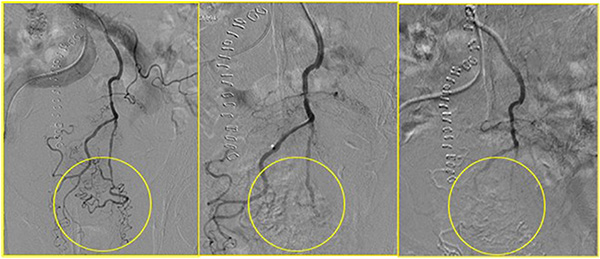

All patients experienced local disease control; in 4/12 cases (33%) we observed an outstanding radiological response with a dramatic reduction in the tumor size which led us to radical surgical resection. (Figures 1, 2, 3). Main result of the volume change is summarized in the Table 2. The Only patient who required DEBIRI twice achievied stable disease.

Figure 3: In yellow circle the pregressive disappearing of the tumor vascular bed during the chemoembolisation.